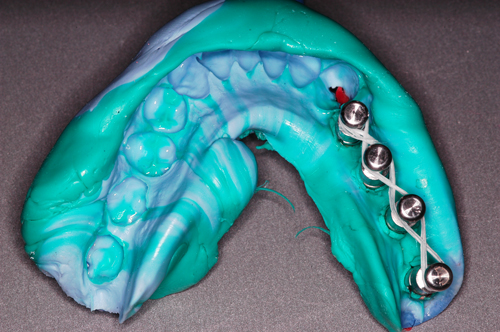

Palabras Clave: ELG: Estereolitográfico OH: Oclusión Habitual ORC: Oclusión en Relación Céntrica Paciente de 35 años de edad ,sexo masculino que lo derivan para implantar el tercer cuadrante. A la auscultación presenta ruidos articulares de tipo chasquido que remiten temporalmente luego de limitación de apertura bucal y maniobras quinesiológicas distractoras. También se observan recidivas de caries en algunos empastes y falta de disclusión canina de ambos lados. Se estudia el caso desde un punto de vista clínico, scanografico mediante Dentascan y tridimensional mediante montaje en articulador. A partir del scanner se obtienen datos para confeccionar modelo estereolitográfico (ELG),operar en el y construir férula quirúrgica dento-muco soportada. Habitualmente se procede directamente a implantar, dado que ese era el requerimiento del profesional derivante y el deseo del enfermo. Sin embargo, esa actitud enmascararía otro tipo de problemas que la boca presenta. Se consulta al odontólogo derivante, y coincide con mi opinión acerca de que si solo se lo implanta, sin corregir la posición mandibular, la situación de las ATMs, los empastes sin anatomía y la falta de disclusiones, el resultado final no será el deseado y su eficacia masticatoria no funcionará optimamente. Consultado el paciente coincide y acepta ese concepto y entonces procedemos a confeccionar un Jig de Lucia a partir del montaje de estudio, y lo dejamos puesto en boca toda la noche anterior a la consulta, para proceder a realizar un ajuste oclusal al día siguiente sin engramas anteriores, lo que facilita no tener que relajar nuevamente con laminillas de Long. En esta etapa pierde el implante correspondiente a la pieza 4.7 que traía en boca. Estabilizado el sistema, procedemos a la parte quirúrgica, comenzando por instalar la férula, retirar opérculos gingivales mediante bisturí circular, fresado óseo e instalación de implantes ,toma de impresión a cubeta fenestrada (pegando con metacrilato sin cambios dimensionales, los transfers a la cubeta especialmente diseñada.(1º método de pasividad protética utilizado), e instalación de tornillos de cicatrización. Inmediatamente de retirada la cubeta de boca y colocadas las réplicas de los implantes, procedemos a ferulizar los “ápices” de las réplicas para que no sufran movimientos durante el llenado de la impresión.(2º método de pasividad protética utilizado). Controlamos radiograficamente Tres meses después, procedemos a tomar nuevos registros de arco facial, registros intermaxilares en Oclusión en Relación céntrica, montaje de los modelos obtenidos intra operatoriamente y confección de un conjunto de cuatro coronas provisionales de metacrilato en el sector implantado y las correspondientes al maxilar superior. Verificada la perfecta función de todos los componentes, ausencia de todo tipo de síntoma y comprobada la paz en todo el sistema, procedemos tiempo después a confeccionar las fundas definitivas, que constituyen el “cerrojo” de la dinámica del mismo. Por último, corroboramos la oclusión fundamentalmente en lo que hace a la: